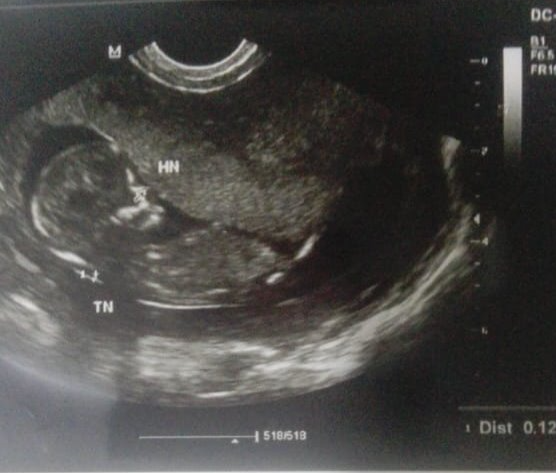

De todos los requerimientos para una alimentación óptima, que garantice la normal producción de Hemoglobina, consideraremos de mucha importancia al Ácido Fólico porque su función va mas allá de nutrir la sangre, es un componente más que necesario, indispensable en la formación estructural de los tejidos. Su importancia radica en la síntesis de purinas, compuestos principales en la creación de la molécula de ADN Y de ARN y con esto nos referimos específicamente a la actividad genética de lo que depende la normal división y la reproducción celular, que es el centro de cualquier forma de vida en crecimiento y desarrollo. En la gestación del ser humano el ácido fólico, es el responsable de la transmisión de las características hereditarias y su deficiencia da origen a Malformación Congénita en el tubo neural que puede ser incompatible con la vida dependiendo del grado de afectación.